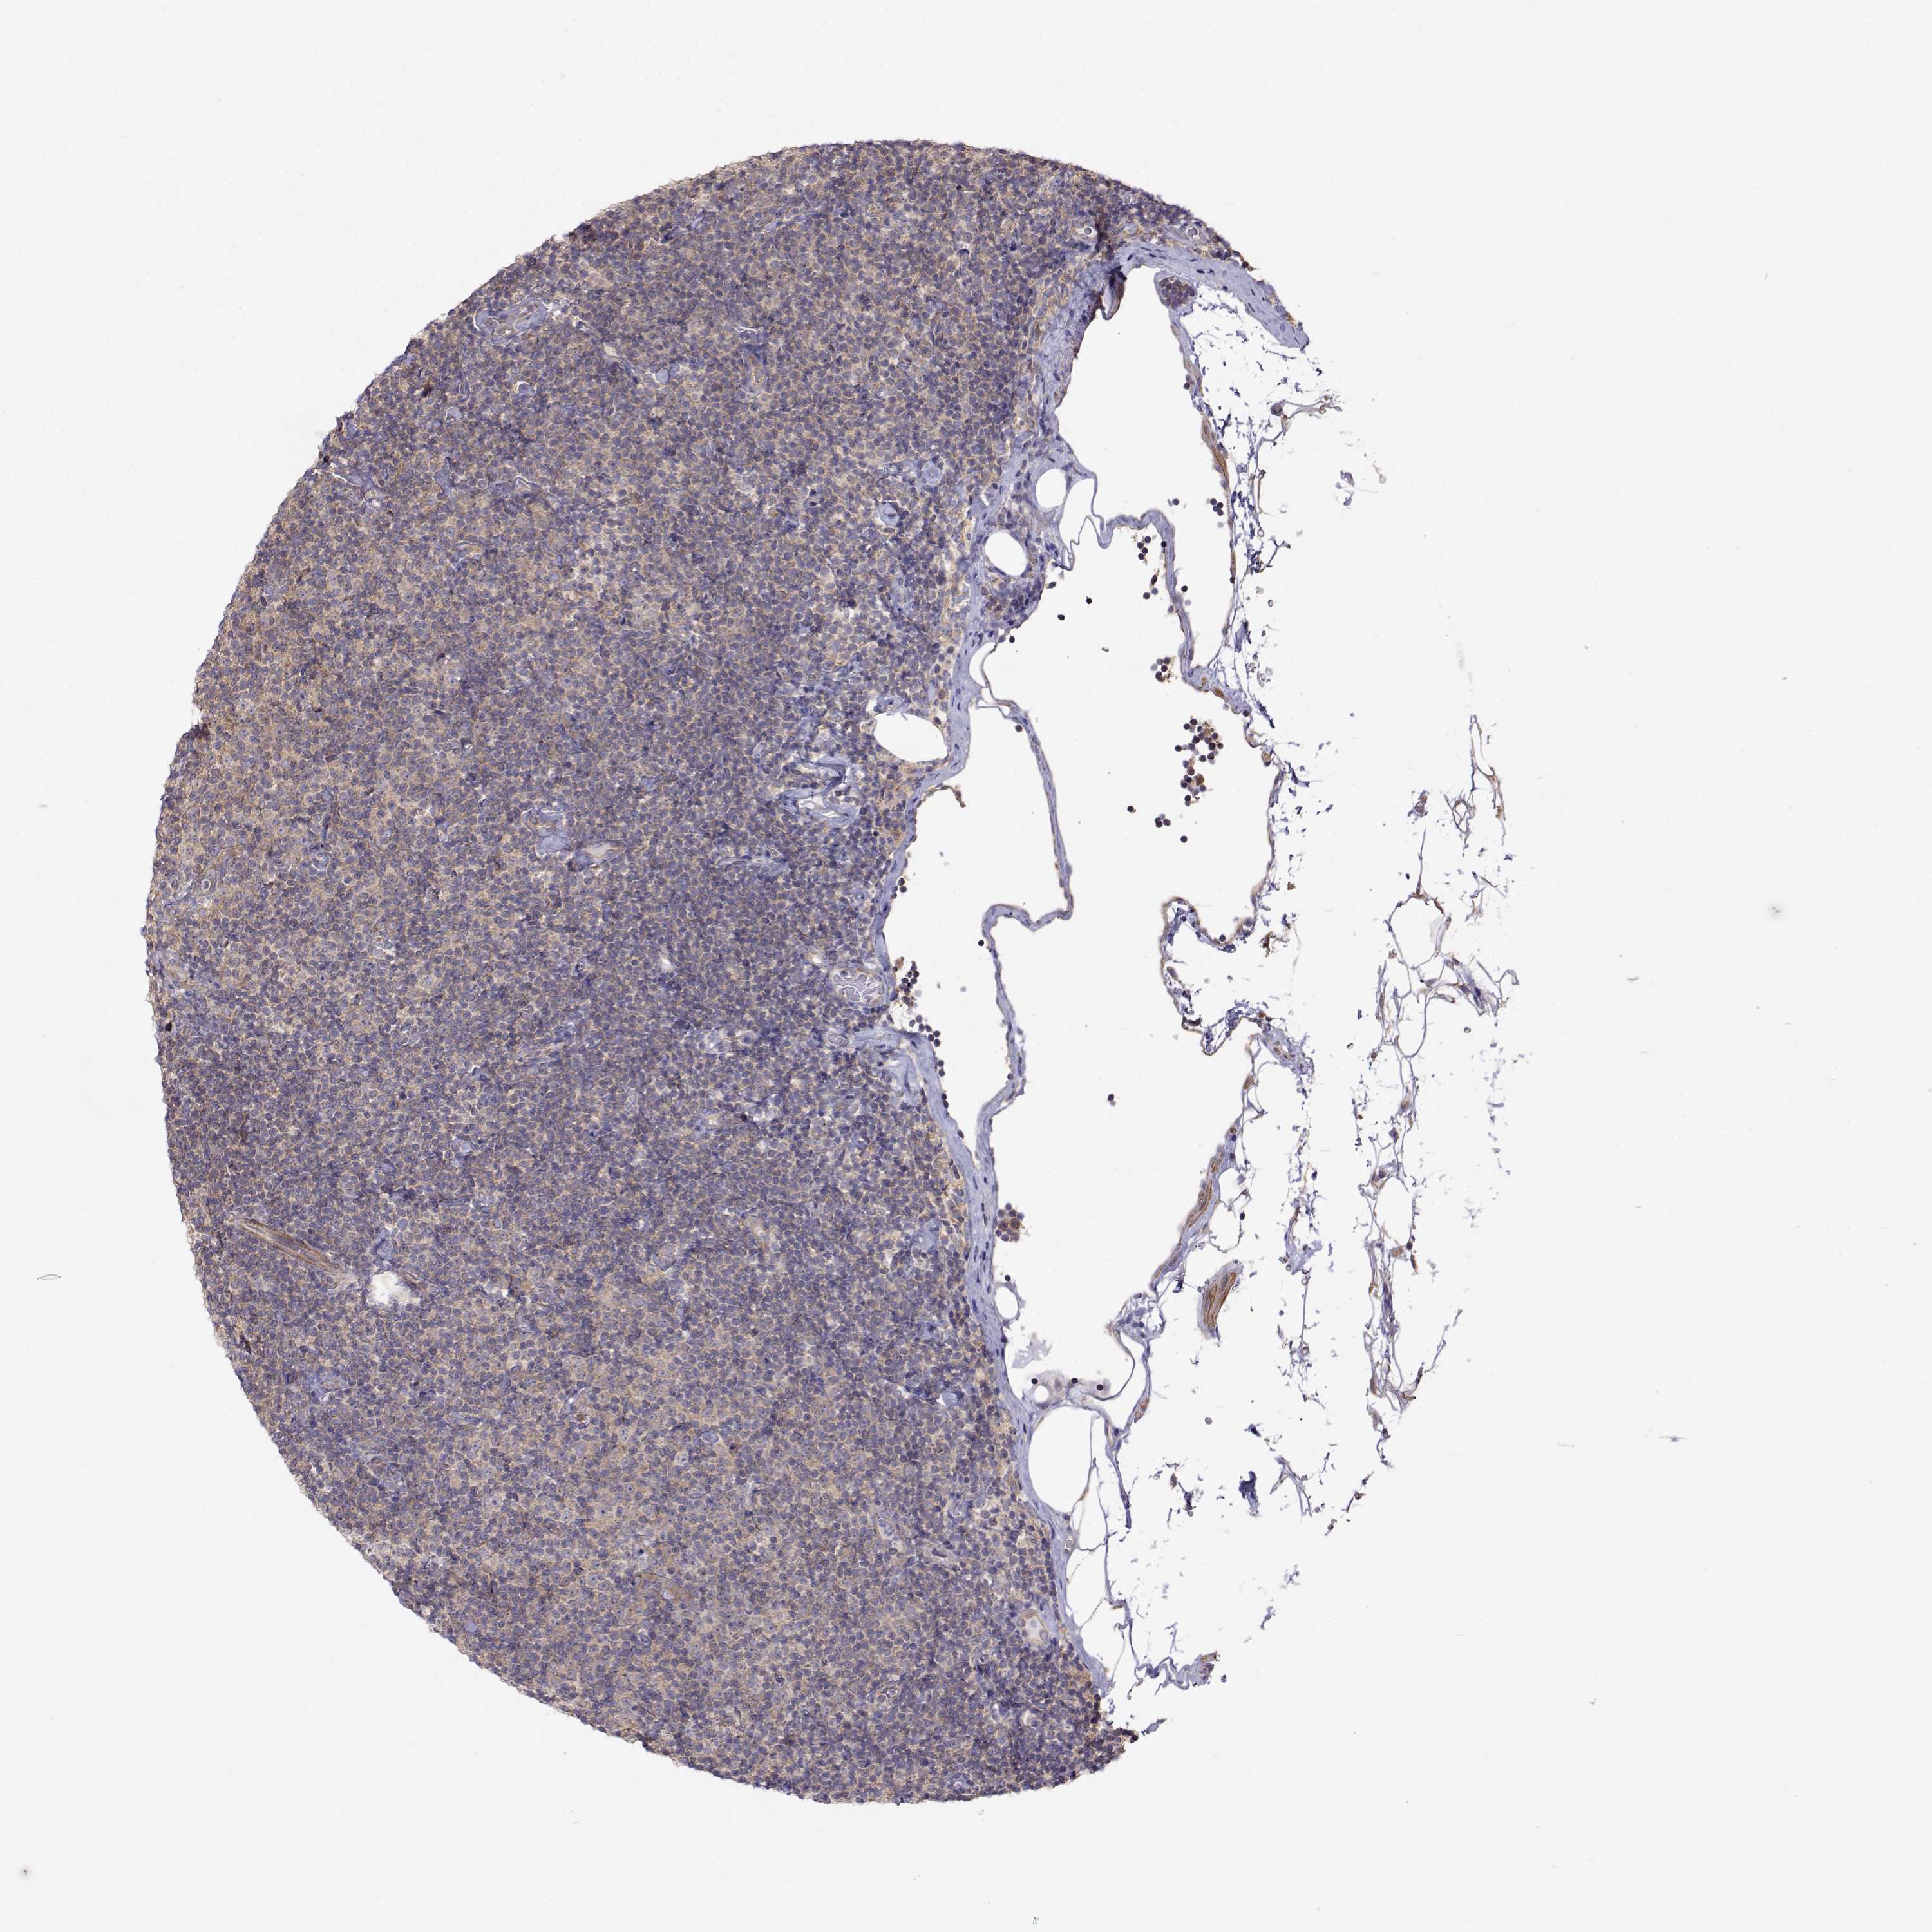

LYMPHOMA - Protein expressioni

A mouse-over function shows sample information and annotation data. Click on an image to view it in a full screen mode. Samples can be filtered based on level of antibody staining by selecting one or several of the following categories: high, medium, low and not detected. The assay and annotation is described here.

Antibody stainingi

Antibody staining in the annotated cell types in the current human tissue is reported as not detected, low, medium, or high, based on conventional immunohistochemistry profiling in selected tissues. This score is based on the combination of the staining intensity and fraction of stained cells.

Each image is clickable and will lead to virtual microscopy that enables deeper exploration of all samples and also displays staining intensity scores, fraction scores and subcellular localization as well as patient and tissue information for each sample.

Antibody HPA073653

Staining

High

Medium

Low

Not detected

Intensity

Strong

Moderate

Weak

Negative

Quantity

>75%

75%-25%

<25%

None

Location

Nuclear

Cytoplasmic/membranous

Cytoplasmic/membranous,nuclear

Malignant lymphoma, non-Hodgkin's type, Low grade

Malignant lymphoma, non-Hodgkin's type, High grade

Hodgkin's disease, NOS